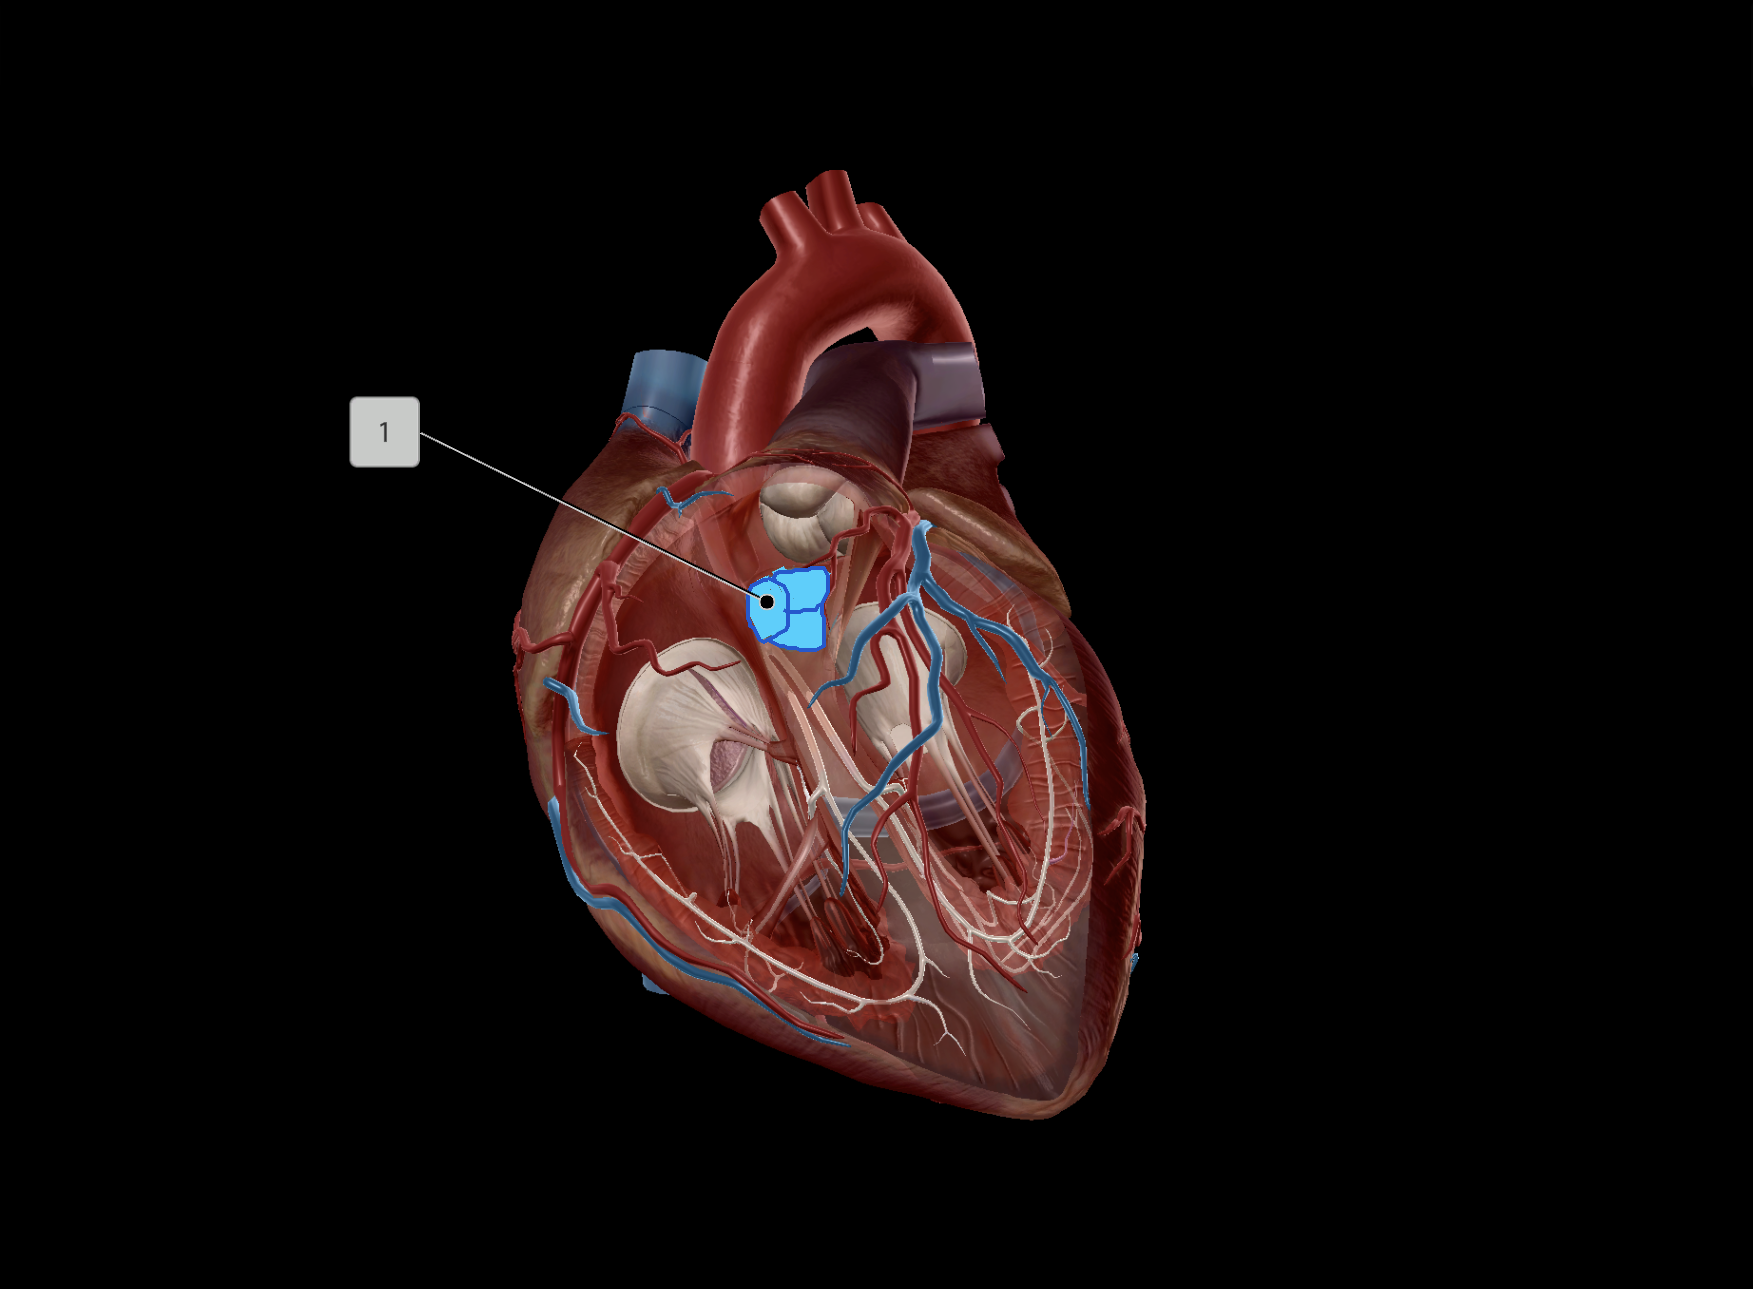

Tricuspid Valve

Bicuspid Valve

Aortic Valve

Papillary Muscle

Pulmonary Valve

Interventricular Septum

Chordae Tendineae